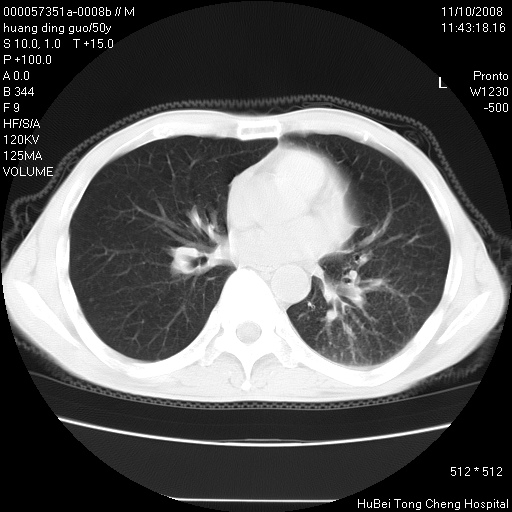

患者 男,50岁。左侧腰背部疼痛3月余,伴消瘦。平素健康,无传染病史。

胸部ct轴位平扫(层厚10mm,螺距1.5,重建间隔10mm),图像如下:

左肺下叶背段有一厚壁空洞,外壁呈锯齿状伴毛刺改变。空洞相邻胸膜有牵拉改变。左肺下叶血管支气管束不规则增粗,小叶间隔增厚。胸椎骨质破坏。考虑左肺下叶周围型肺癌伴左肺下叶癌性淋巴管炎、胸椎转移。

左肺下叶背段有一厚壁空洞,外壁呈锯齿状伴毛刺改变。空洞相邻胸膜有牵拉改变。左肺下叶血管支气管束不规则增粗,小叶间隔增厚。胸椎骨质破坏。考虑左肺下叶周围型肺癌伴阻塞性肺炎、胸椎转移。其他待排

左肺下叶背段有一厚壁空洞,内壁不规则,外壁呈锯齿状伴毛刺改变。空洞相邻胸膜有牵拉改变。周围呈絮状炎性改变,左肺下叶血管支气管束不规则增粗,小叶间隔增厚。胸椎骨质破坏。考虑左肺下叶周围型肺癌伴左肺下叶阻塞性肺炎、胸椎转移。